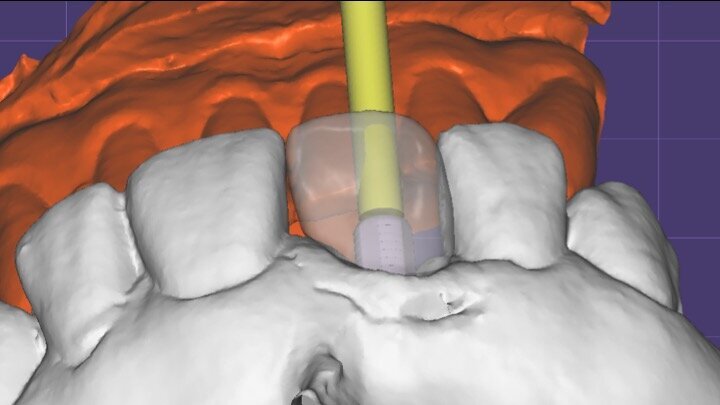

Figura 6. A pesar del defecto óseo, siempre buscamos la posibilidad de crear un nuevo alveolo quirúrgico que emerja por la zona del cíngulo de los dientes adyacentes, es decir, el margen de emergencia adecuado. En estos defectos, intentamos siempre el anclaje en profundidad con implantes largos de unos 16 mm debido al gran defecto existente. Es la única forma de que la estabilidad primaria del implante permita realizar una Prótesis Inmediata.

Figura 7. Implante de conexión interna insertado 2 mm por debajo de la cresta ósea, independientemente del defecto existente y a 55 Nw. Al no existir margen vestibular, tomamos como referencia los dos picos óseos de las papilas y entre ellos trazamos una línea imaginaria que los una enterrando el hombro unos 2 ó 3 mm por debajo de ella.